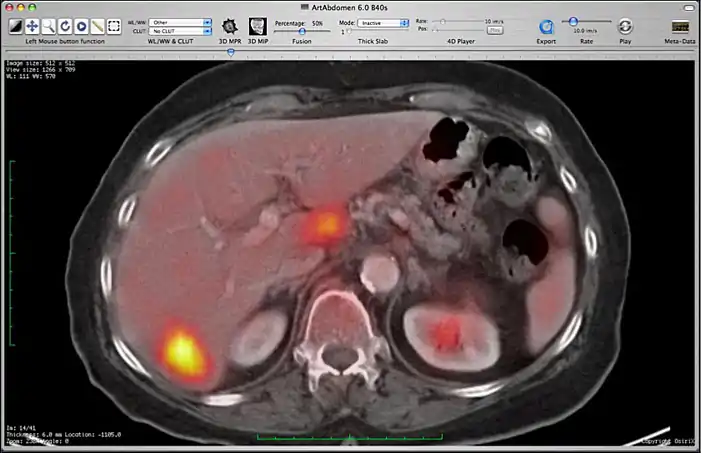

Image fusion between a CT and PET series.

You can control the fusion intensity with the “Fusion Percentage” slider from the toolbar. Note that if you close one of the two series, the fusion will be stopped. If you make a modification on the first series (CLUT, zoom, rotation, ...), these modifications will be applied to the second one.